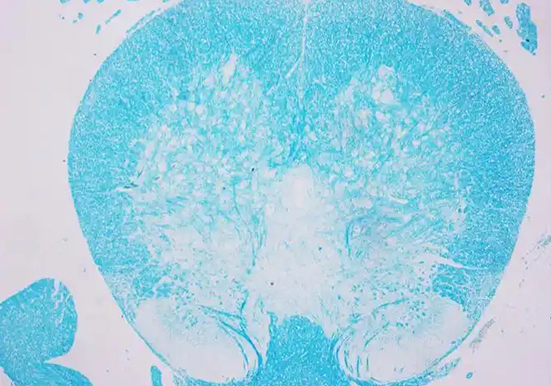

LFB 染色即劳克坚牢蓝(Luxol Fast Blue)染色,是一种常用于显示神经组织中髓鞘结构的染色方法,以下是关于它的详细介绍:

染色原理:LFB 属于铜 - 酞箐染料,是一种酒精溶性染料。髓鞘由髓鞘细胞和细胞膜组成,其成分主要是类脂质和蛋白质,其中的脂蛋白与 LFB 染料发生酸 - 碱反应,脂蛋白碱基取代 LFB 染料的碱基,形成深蓝色沉淀,从而使髓鞘着色。